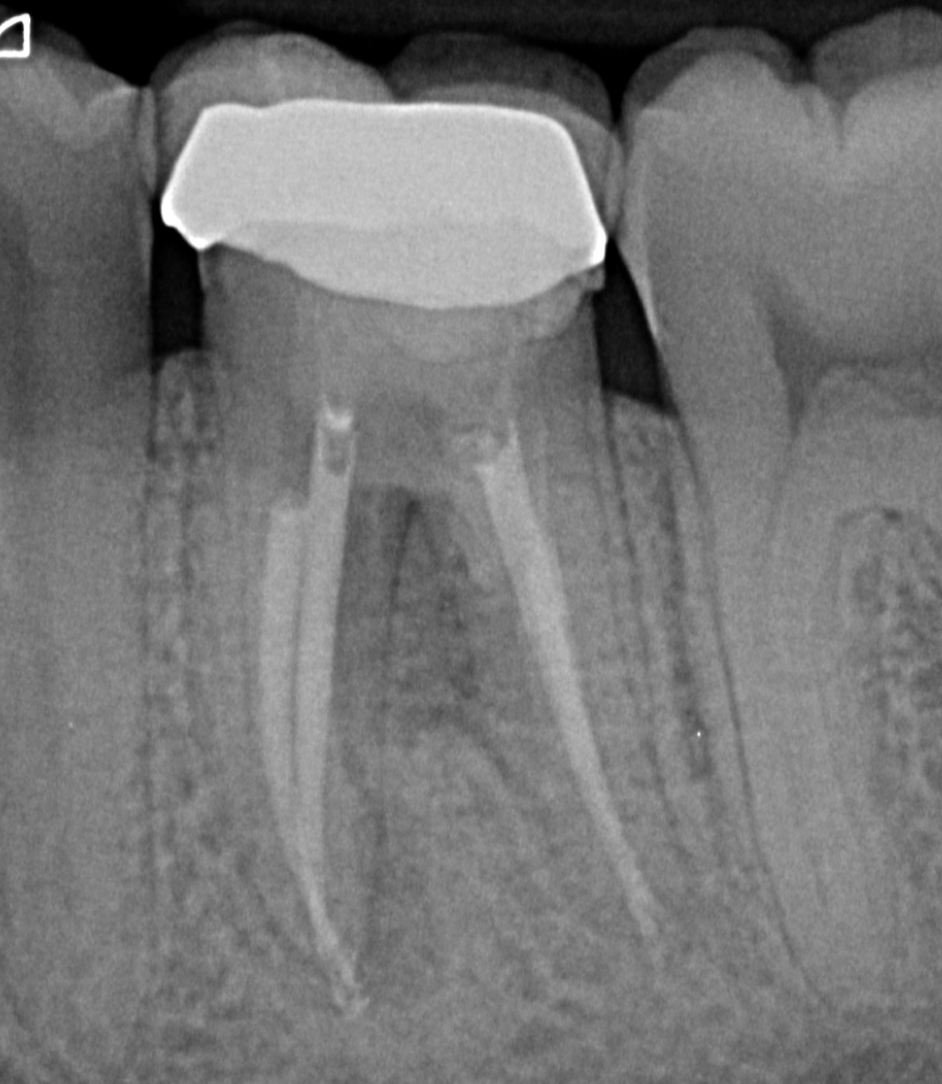

Radiographic assessment demonstrated an inadequately treated root canal system, accompanied by a radiolucency in the furcation region. These findings raised a strong suspicion of a procedural complication, most likely a perforation (Fig. 1).

Access refinement was performed under rubber dam (Fig 2) and dental operating microscope to allow enhanced visualisation. Upon careful inspection, a pulpal floor perforation was clearly identified in the furcation area, adjacent to the distal canal (Fig. 3). The defect exhibited active bleeding and a direct communication with the periodontal tissues, confirming its biological significance and potential impact on prognosis.

Further evaluation of the canal system revealed incomplete debridement, with evidence of insufficient canal preparation and the presence of residual intracanal medicament (Fig. 3). These findings indicated suboptimal prior treatment and contributed to the persistence of symptoms.